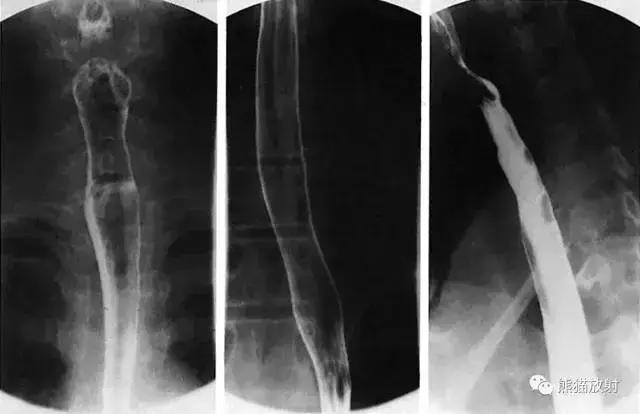

三、食管

图5 食管造影

图6 食管解剖图示。1 悬雍垂,2 舌会厌外侧襞,3 会厌,4 梨状隐窝,5 食管上括约肌,6 食管体部,7 主动脉弓,8 支气管及主动脉段,A 气管旁段,B 主动脉段,C 支气管段,D 支气管间段,E 心后段,F 膈上段